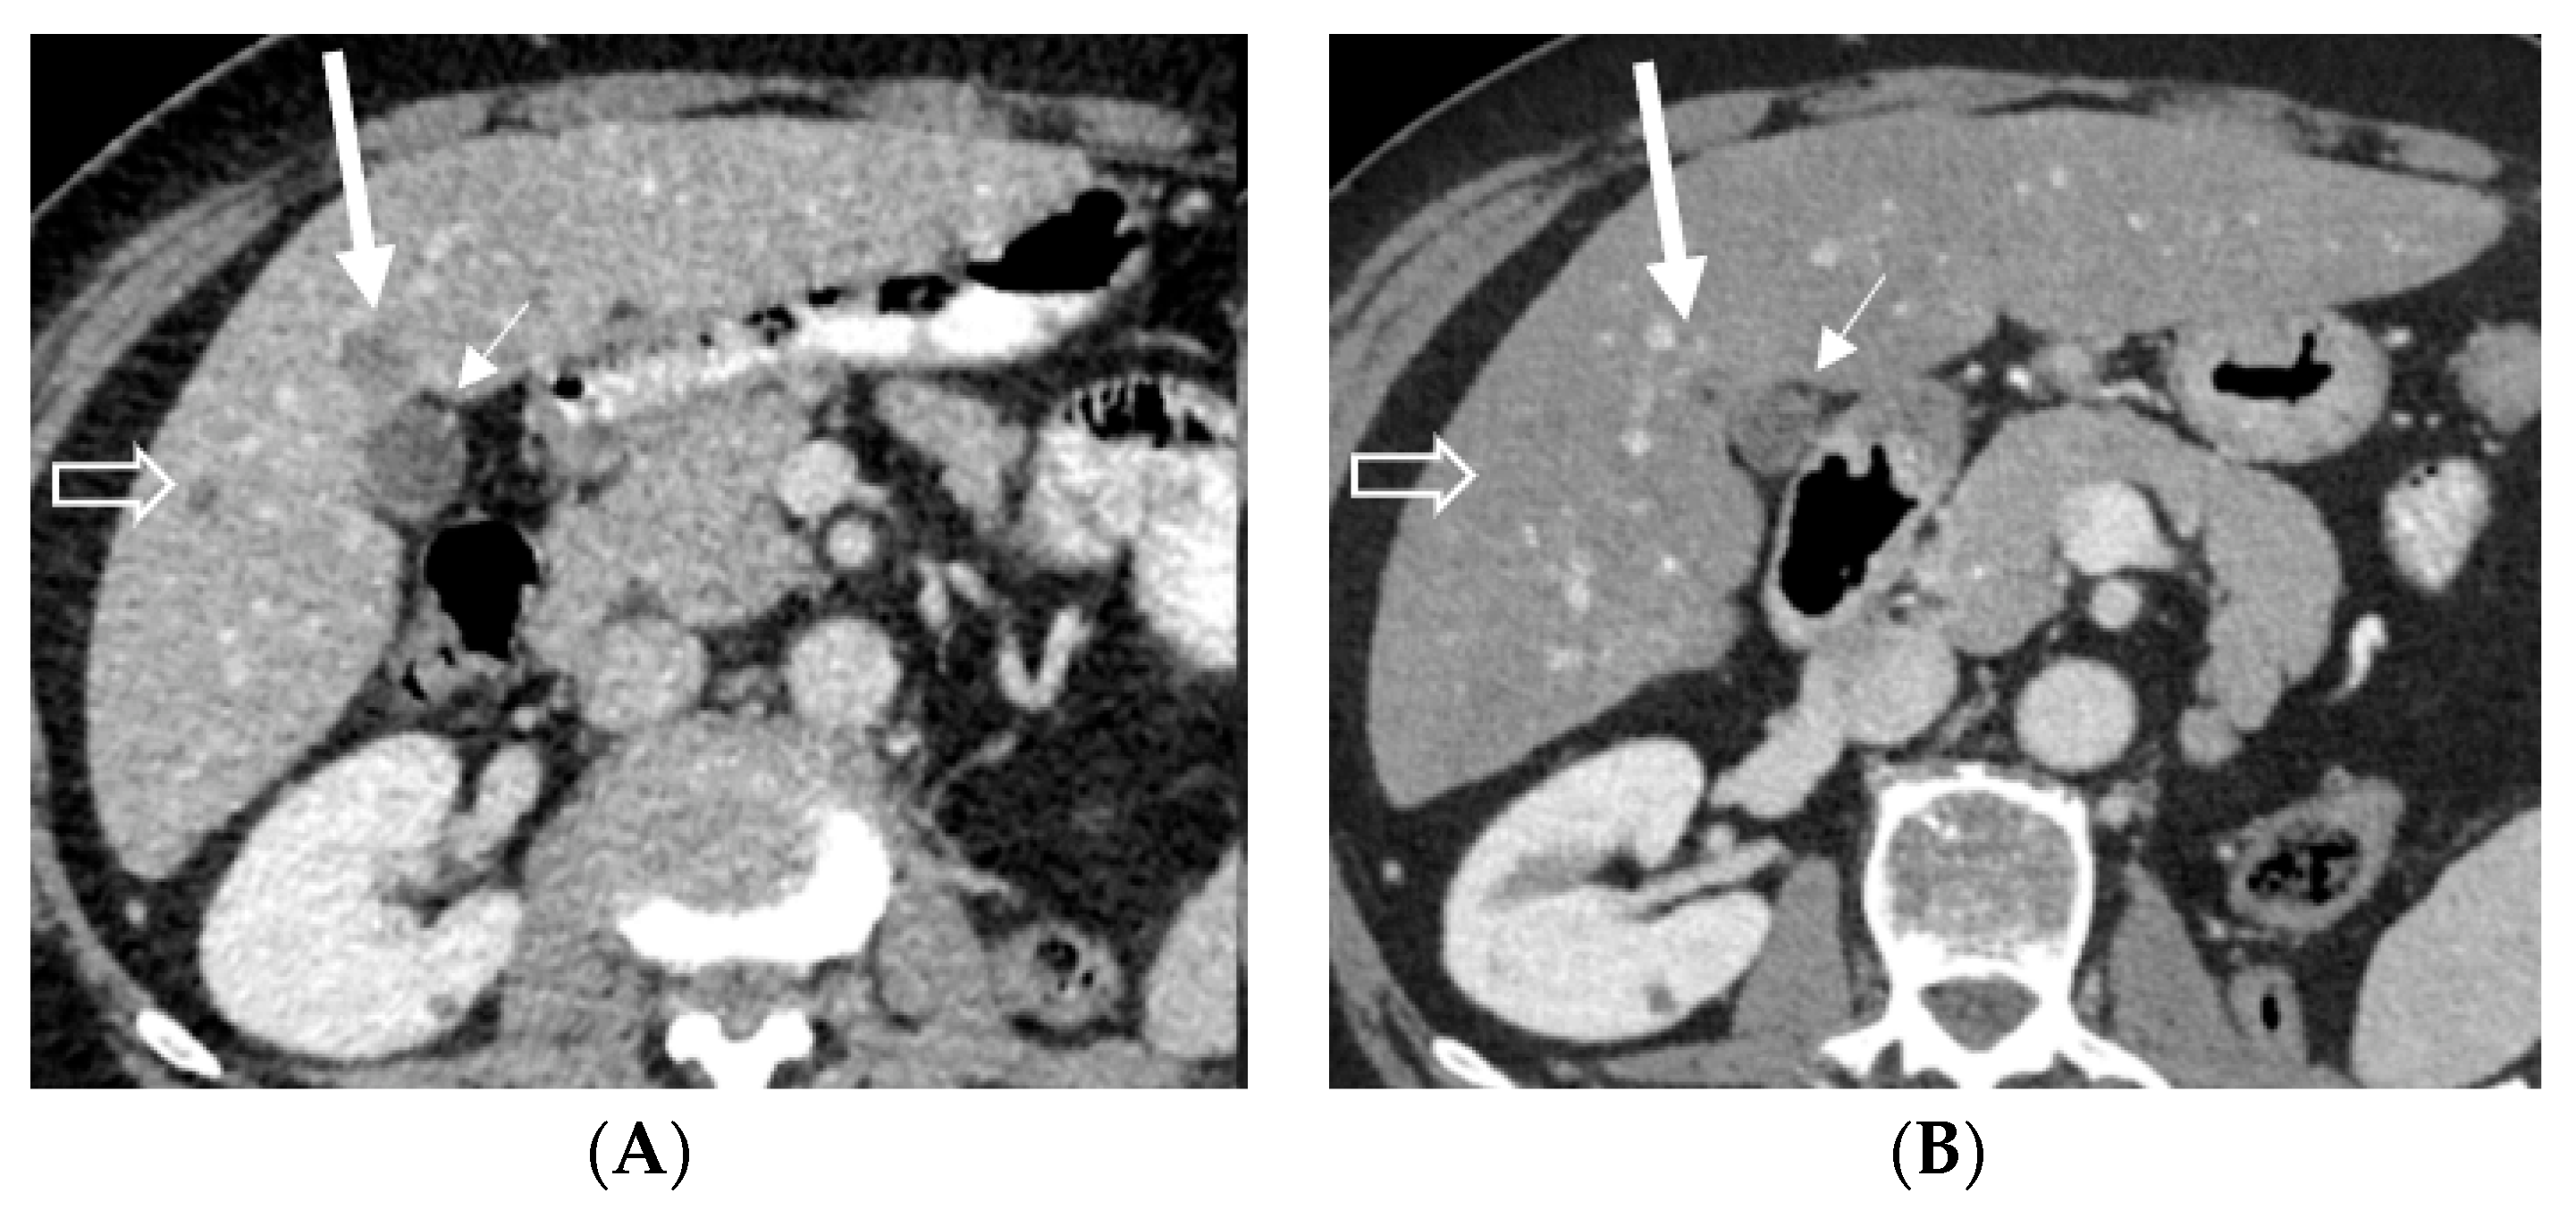

2.1. Case 1

2.2. Case 2

2.3. Case 3